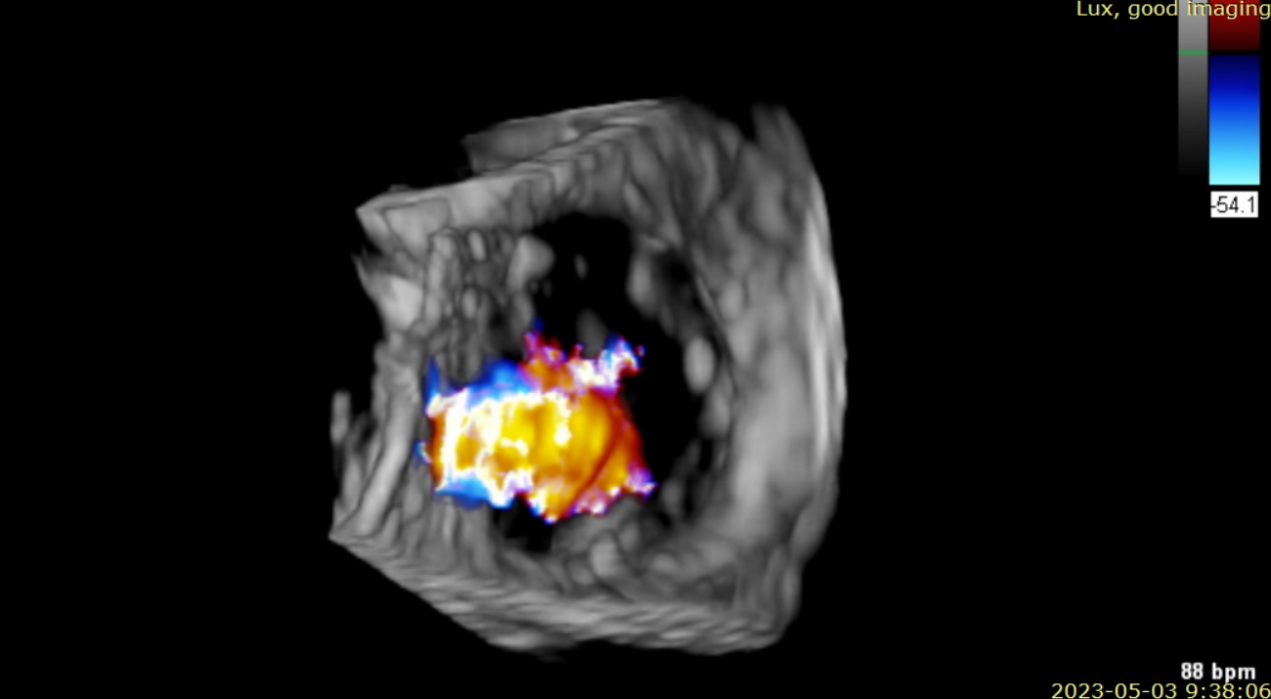

近日,美國紐約Montefiore醫(yī)學中心(Montrefiore Medical Center)的Azeem Latib教授團隊成功應用LuX-Valve Plus經(jīng)血管三尖瓣置換系統(tǒng)為兩位三尖瓣大量反流的患者完成三尖瓣置換手術。術后超聲顯示人工三尖瓣植入穩(wěn)定,瓣葉啟閉良好,僅殘余微量瓣周漏?;颊哂谑中g室即刻拔除氣管插管,血流動力學改善顯著。此次手術是LuX-Valve Plus于紐約的首次臨床應用,治療效果優(yōu)異。

術前超聲提示大量三尖瓣反流

術后超聲提示無瓣周漏